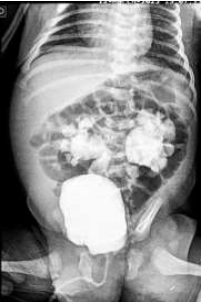

RN nasceu de parto vaginal, com APGAR 5 e 6, apresentando desconforto respiratório de imediato, caracterizado

por gemência, tiragem subcostal e taquipneia. A idade gestacional pela DUM foi de 31 semanas. RN foi levado à UTI

neonatal, com piora importante do desconforto respiratório, necessitando de intubação orotraqueal. Neonatologista

solicitou RX de tórax (imagem abaixo). Genitora relatou perda de líquido vaginal um dia antes do parto, porém,

como foi em pequena quantidade e não teve contrações, decidiu ficar em casa. Somente foi à maternidade, 20 horas

após a ruptura das membranas, em função da intensidade forte e frequente das contrações. RN nasceu cerca de

duas horas após admissão da gestante na maternidade. Dados pré-natais: Gesta IV/ Aborto II. O cartão da gestante

mostrou apenas quatro consultas, com exames realizados somente no primeiro trimestre (todos normais).

Sobre este paciente, analise as assertivas abaixo:

I. Uma das hipóteses diagnósticas para esse RN é de pneumonia pelo Streptococcus do grupo B, sendo indicada antibioticoterapia com penicilina cristalina e gentamicina.

II. A prematuridade e o padrão radiológico tornam a Síndrome do Desconforto Respiratório um dos principais diagnósticos desse paciente.

III. O RN deverá receber uma dose de surfactante exógeno o mais rapidamente possível; estudos recentes mostram a ineficácia de doses subsequentes de surfactante, além do elevado risco de pneumotórax.

IV. A hipóxia perinatal, prematuridade e ausência de corticoide pré-natal são fatores de risco para uma produção insuficiente de surfactante pelos pneumócitos tipo I ainda na vida intrauterina.

Podemos afirmar que